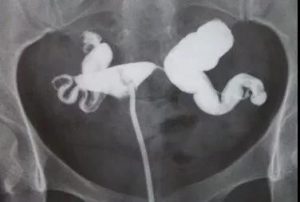

如果患者的双侧输卵管都有明显积水的话,这类患者在胚胎移植前需要进行双侧输卵管切除,若单胚胎移植失败,则面临再次取卵,输卵管切除术后,卵巢功能也会有所下降,再次取卵,获卵数目会减少,可用胚胎也会相应减少。